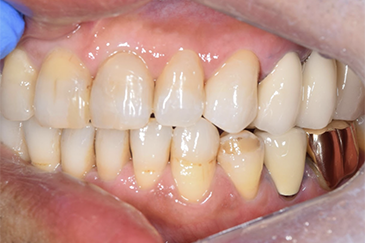

| 年齢・性別 | 50代・男性 |

| 主訴と治療部位 | 前歯の形が気になる。 右上2~左上3番 右下2~左下2番 |

| 治療内容 | ジルコニアステイン |

| 治療費 | 合計1,152,500円 内訳 ジルコニアステイン 1本121,000円×9本1,089,000円 仮歯 1本5,500円×9本 合計49,500円 歯周病治療 歯石除去 SC全顎 約2,000円(保険診療3割負担) SRP全顎 1回約2,000円×6回 合計約12,000円(保険診療3割負担) (2025年1月現在) |

| 治療期間 | 約1年 |

| リスク・副作用 | セット後かみ合わせが高い・きついなどの違和感を覚えることがあります。 神経を残して削った場合、しみる・噛んだ時に痛むなどの症状がでることがあります。 |

| 治療方針 | 歯周病がかなり進行しており歯周病治療と同時進行で古い被せ物を除去し仮歯に置き換えました。 仮歯を何度か修正し歯ぐきが安定したのを確認し最終的な被せ物を作製しました。 |

| 特記事項 | 仮歯はプラスチック製のため取れやすく壊れやすいため、仮歯装着期間中は固いもの・粘着質なものを控えていただく。 |

| 担当者所見 | 今後他の歯の虫歯治療と定期的なクリーニングにて経過を診ていきます。 |